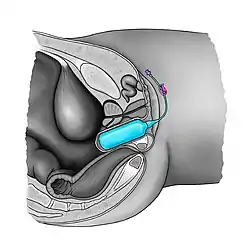

Vaginal dilators, also called vaginal stents or vaginal expanders, can be inflatable and are used during surgeries.[5][6] Vaginal stents are routinely used in postoperative care for transgender patients who have undergone vaginoplasty as part of gender confirmation surgery. They are also used for various conditions, such as vaginal agenesis.[7] The vaginal expander is used immediately after surgery to keep the passage from collapsing, and regularly thereafter to maintain the viability of the neovagina. Frequency of use requirements decrease over time, but remains obligatory lifelong.[8][9]

With solid vaginal dilators, the patient starts with the smallest dilator size, then gradually increasing until the largest dilator size is reached. This practice can be accompanied by breathing exercises in order to relax the pelvic floor muscles. Dilation acts should not cause pain or bleeding.[10] Dilatation with rigid dilators must be done carefully as vaginal perforation and urethral injury may occur.[11][12] There is no consensus on the frequency and duration of using vaginal dilators.[13] In case of vaginal expanders, the therapist or the patient introduces the deflated balloon into the vagina and then inflates it gently until the required diameter is obtained.[7]